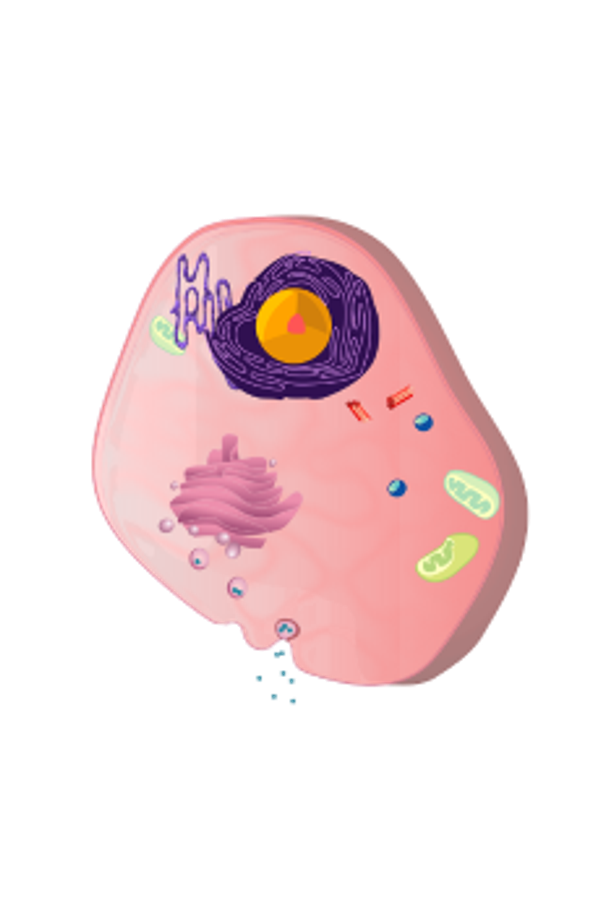

Die kleinen Partikel, die in den Blutkreislauf aufgenommen werden, sind dann wichtig für den Stoffwechsel unseres Körpers. Ein anderes Wort für Stoffwechsel ist Metabolismus, das aus dem Griechischen kommt und Umwandlung bedeutet. Kurz gesagt geht es dabei um die Umwandlung von Nährstoffen aus der Nahrung in Substanzen, die Energie liefern und uns das Leben ermöglichen. Der Stoffwechsel findet in vielen Organen und Körperzellen unseres Körpers statt, was ihn zu einem sehr speziellen und sehr komplizierten Prozess macht.

Alle diese Vorgänge, die das Funktionieren unseres Körpers ermöglichen, werden als Stoffwechsel bezeichnet. Der Stoffwechsel selbst besteht aus zwei verschiedenen, sich ergänzenden Prozessen, nämlich dem Katabolismus und dem Anabolismus. Unter Katabolismus versteht man den Abbau von Kohlenhydraten, Fetten und Proteinen zur Energiegewinnung, die als Brennstoff und für die Muskeltätigkeit verwendet wird.

Anabolismus bedeutet, dass die Nahrung im Körper gespeichert wird, damit die Energie für das Wachstum und die Abwehr von Eindringlingen, die Krankheiten oder Infektionen verursachen können, genutzt werden kann. Überschüssige" Energie wird in Fett umgewandelt.

Der größte Teil unserer Energie stammt aus der Aufspaltung von Kohlenhydraten in Zucker (Glukose). Wenn nicht genügend Glukose in Energie umgewandelt werden kann, sind Fette und Proteine die vorgesehenen Energielieferanten. Fett wird zunächst in der Leber in Glycerin umgewandelt, das dann in Glukose umgewandelt wird. Proteine werden in Aminosäuren aufgespalten. Diese Aminosäuren werden für das Wachstum, aber auch für die Arbeit der Enzyme in den Zellen benötigt.